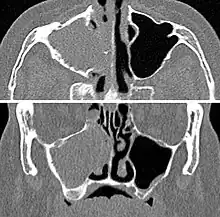

Maxillary sinusitis caused by a dental infection associated with periorbital cellulitis

Frontal sinusitis